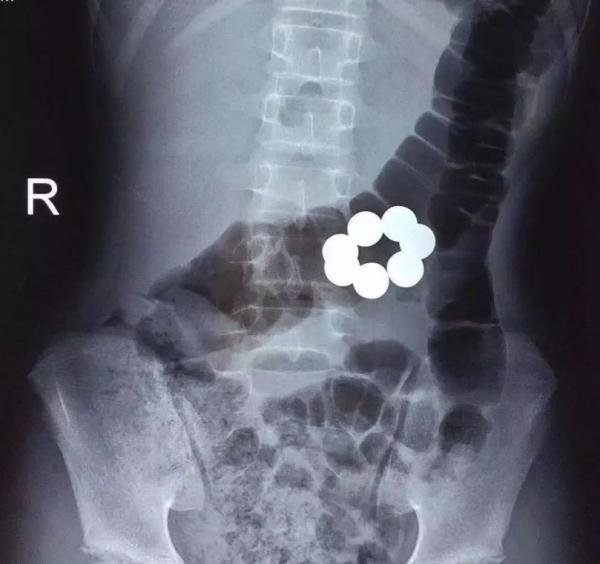

2、最危險的“急診玩具”——磁力珠。

磁力珠又稱巴克球,因為帶有磁性,可根據孩子的想象組合成各種各樣的造型,有助於開發孩子的創造力和空間思維能力,因此曾風靡一時。但由於磁力珠色彩鮮豔且形狀圓潤,很多孩子易將其當作糖豆吞下。與糖豆不同的是,這一顆小小的磁力珠磁力高達4000高斯(國際規定玩具磁力上限為50高斯)。這些磁力強大的磁力珠進入消化道後,磁力珠之間會相互吸引,導致胃腸道貼在一起進而缺血壞死,危及患兒生命。隨著近年來相關醫學科普的推廣,磁力珠已慢慢淡出兒童玩具市場,但是仍可在一些益智玩具上看到磁鐵的零部件,我們門診、急診中也會接診各種把磁鐵類零部件誤吞下的患兒,這需要引起爸爸媽媽們的重視。